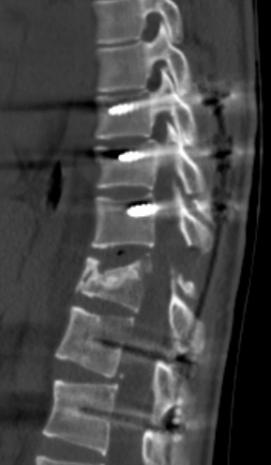

CT提示脊髓脊柱严重损伤

· T11椎体严重骨折变形

· 脊柱内固定跨越6个节段

· 双下肢肌电信号无法引出